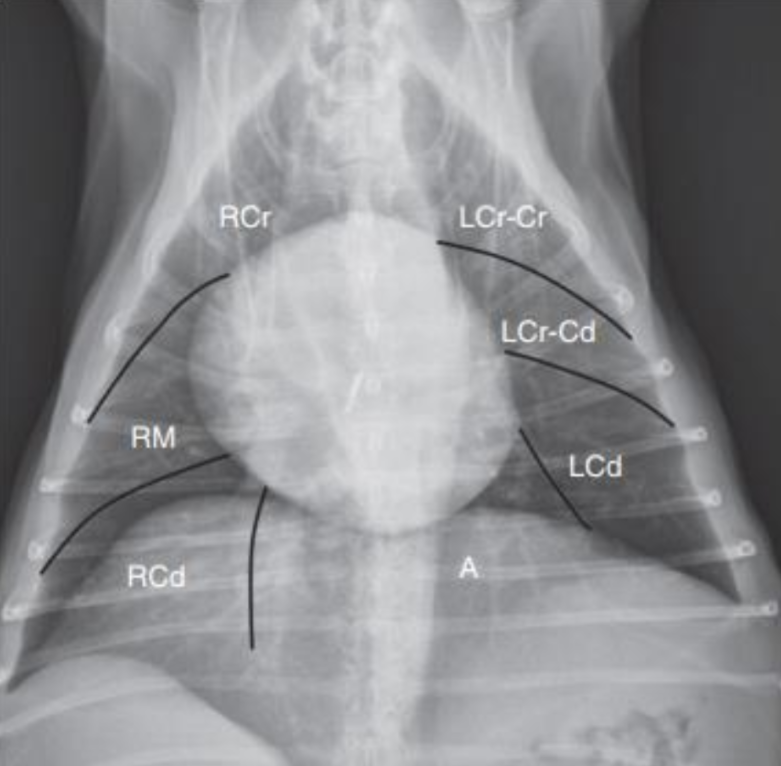

1. Normal Anatomy

| Thorax | |